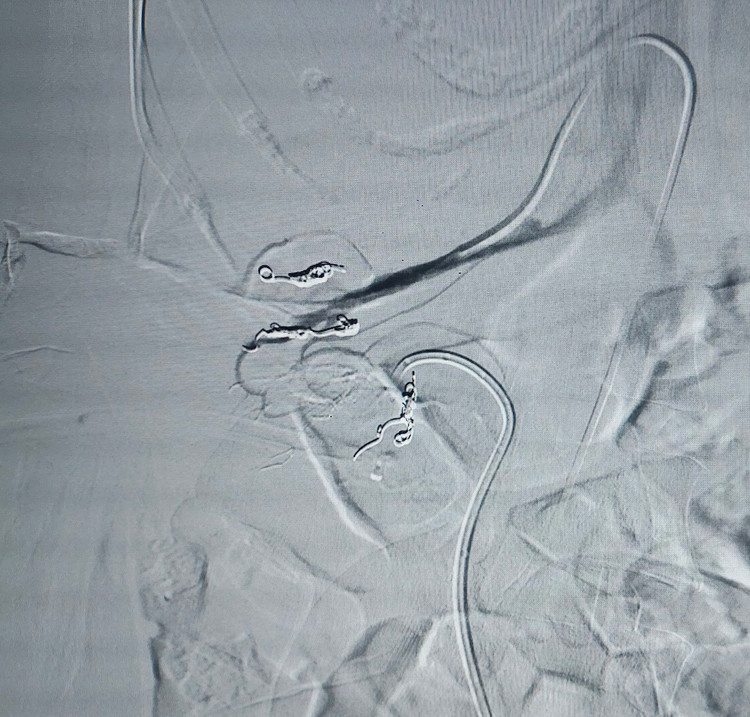

![]() |

| Hình số 2. |

Trước khi làm ca can thiệp, TS.BS Nguyễn Ngọc Cương cùng đồng nghiệp cũng đã tính đến các biến chứng có thể:

- Tắc động mạch phổi cấp do huyết khối bám trên bề mặt sonde dẫn lưu bị “tuốt” theo chiều dọc rồi bắn về tim

- Chảy máu từ vết rách tĩnh mạch vào đường bài xuất

- Nước tiểu rò vào mạch máu gây nhiễm trùng huyết, gây kích hoạt huyết khối tĩnh mạch ồ ạt

… Biến chứng nào cũng có thể chết người rất nhanh.